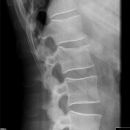

BWK 5 Fraktur